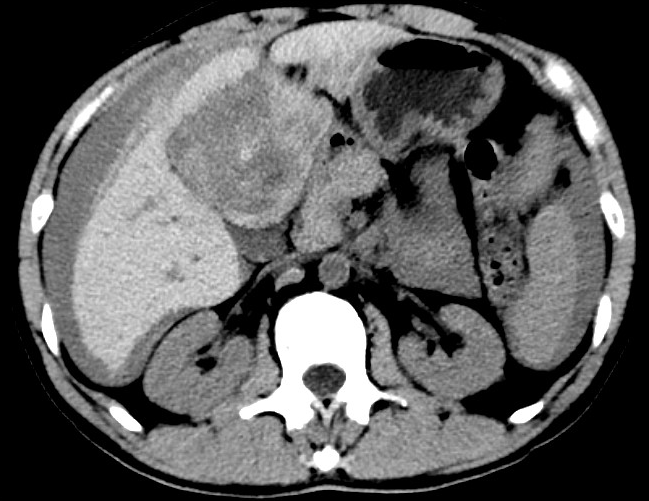

放下電話的白葦急赴消內(nèi)三搶救室會診,經(jīng)仔細(xì)查體、對患者腹部CT進(jìn)行詳細(xì)閱片、綜合評估患者后,考慮患者是肝占位破裂出血?;颊卟∏槭志o急、一刻也不容耽誤,需立刻急診行肝動脈造影 栓塞術(shù)進(jìn)行止血治療,在與患者家屬溝通后,立即通知消化介入室準(zhǔn)備急診手術(shù)。

入手術(shù)室時,患者神志迷糊,口唇干燥、重度貧血貌,心電監(jiān)護(hù)提示:心率140-160次/分,血壓70/43mmHg,這是失血性休克的表現(xiàn)!白葦快速建立靜脈通道緊急給予輸血,升壓,止血等液,立即給予肝動脈造影,術(shù)中發(fā)現(xiàn)肝左葉疑似腫瘤病灶、病灶周圍血管分支有造影劑外溢,考慮血管破裂出血,迅速給予栓塞微球進(jìn)行肝動脈栓塞。整個手術(shù)過程不足20分鐘,術(shù)后即刻患者心率降至100-110次/分、血壓升至90/60mmHg。

術(shù)后給予積極抗炎,止血,保肝、利尿等對癥治療,復(fù)查血常規(guī)提示活動性出血停止后,在超聲引導(dǎo)下行腹腔穿刺引流術(shù),術(shù)后3天共引流出血性腹水約4000ml?;颊呓?jīng)復(fù)查各項(xiàng)指標(biāo)均趨于正常,復(fù)查CT提示腹腔積血已基本吸收,患者康復(fù)出院。